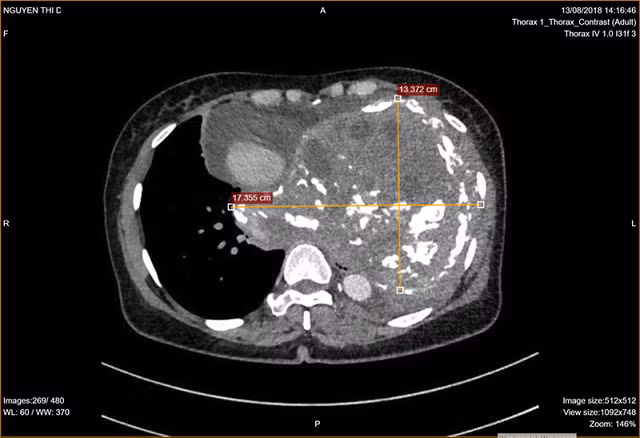

Bệnh nhân được chỉ định thực hiện các kiểm tra hình ảnh. Trên kết quả CT-Scan, bác sĩ cũng “giật mình” trước hình ảnh khối u lớn chiếm gần hết lồng ngực bên trái của người bệnh. “Đây là dạng khối u tân sinh nằm ở trung thất, chưa rõ tính chất. Khối u có kích thước rất lớn (17x13x12cm) đẩy lệch tim, khí quản, thực quản của bệnh nhân sang lồng ngực phải, xâm lấn động mạch chủ ngực đe dọa trực tiếp sinh mạng người bệnh”, BS Nguyễn Kim Anh, Trưởng khoa Lồng ngực Mạch máu cho hay.